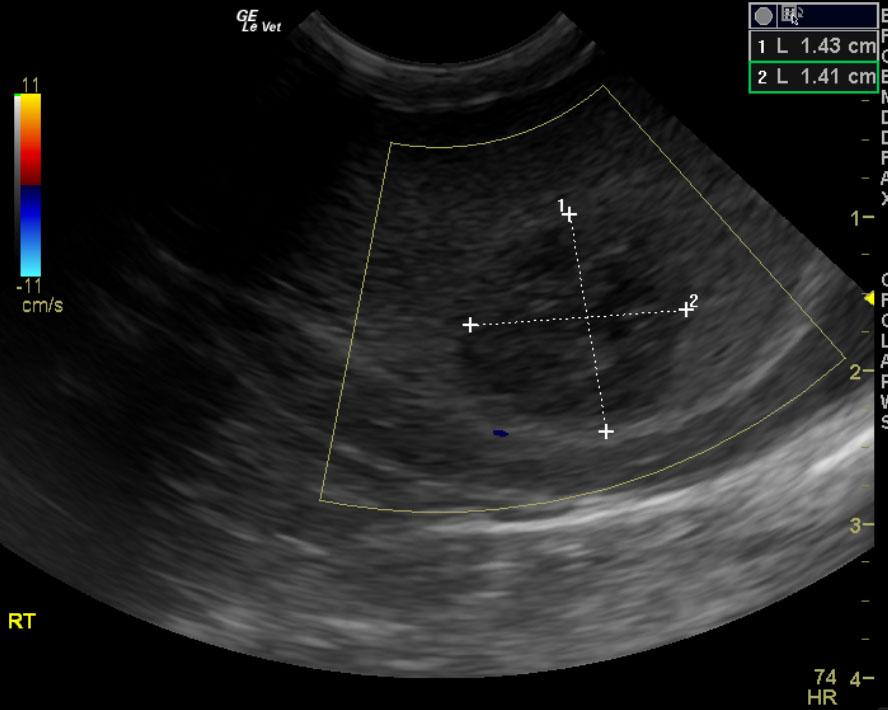

A ten year old intact male labrador retriever was presented with an enlarged prostate and painful rear end. Serum biochemistry and CBC were within normal limits. The urine specific gravity was 1.022 with mild pyuria.